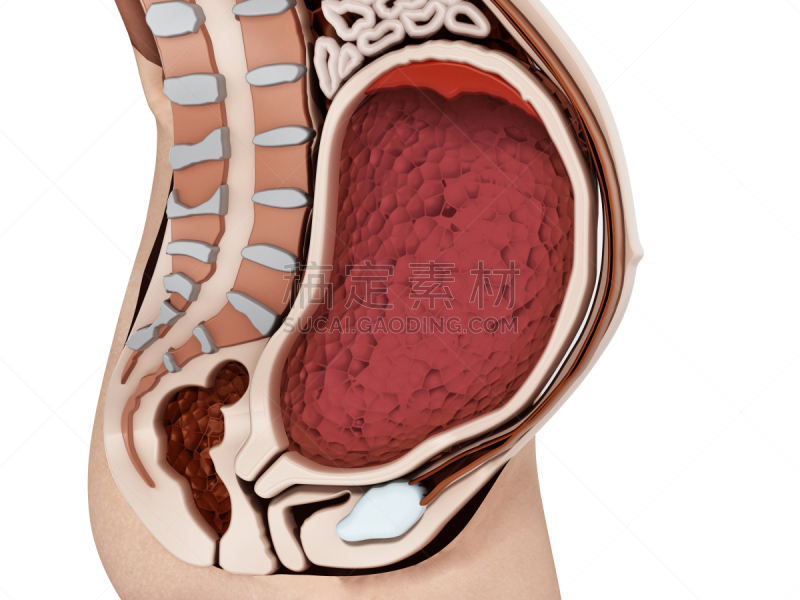

有胚胎的孕妇详情